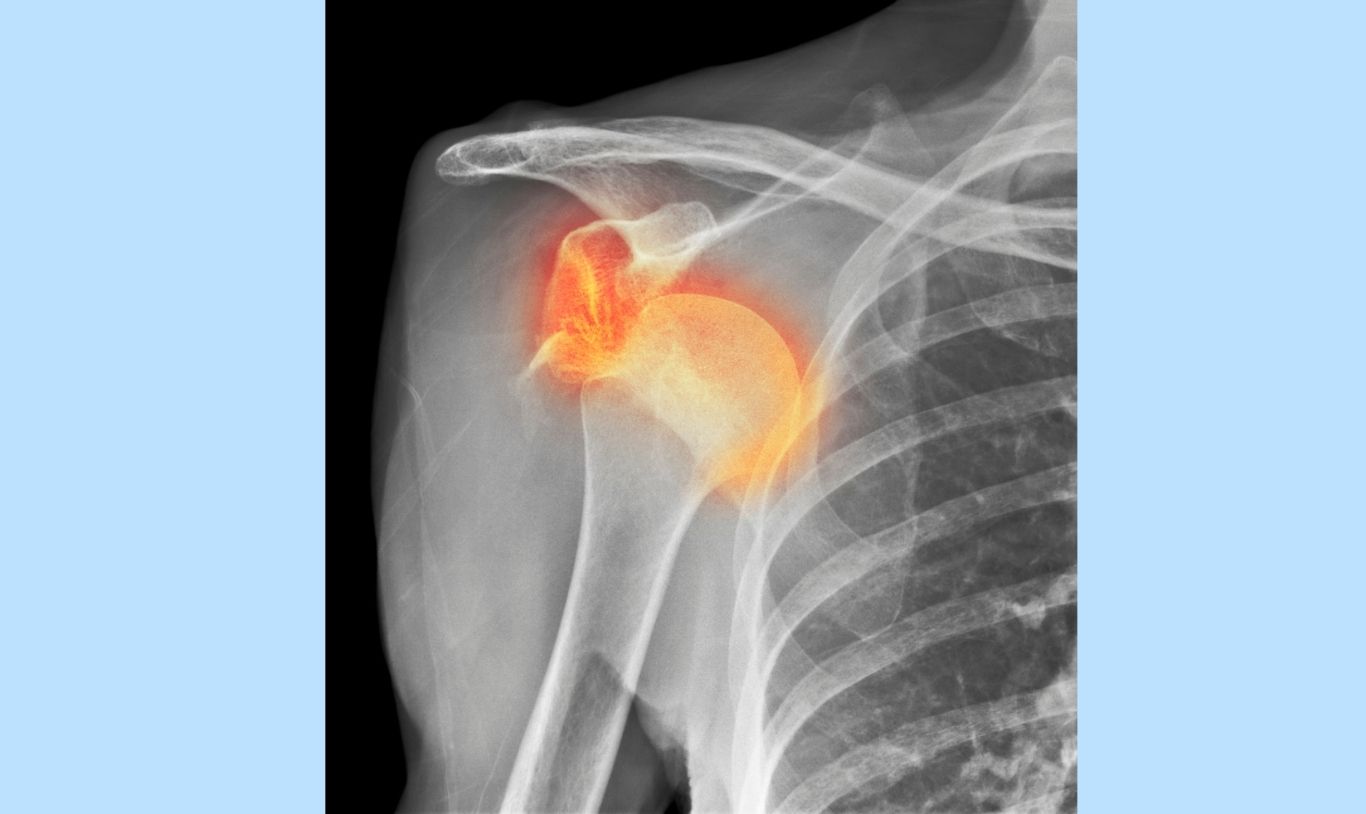

Common Rugby Injuries: Rugby Shoulder

Common Rugby Injuries: Rugby Shoulder (by Sportsperformance Physiotherapy)

Rugby is an intense contact sport. Shoulder injuries are very common in rugby. They include:

Common Rugby Shoulder Injuries

• Dislocated Shoulders: A player can dislocate their shoulder, resulting in damage to the muscles and ligaments. These require immediate medical attention, i.e. being put back in place, as soon as possible to prevent further damage. Recurring shoulder instability is very common after a dislocation. Optimal rehabilitation is essential for stability after dislocation.

• Muscle Strains: The rotator cuff can be strained or torn during acute events, or develop over time due to repetitive, forceful movements (i.e. overuse injury).

• AC Joint Injuries: This small joint at the shoulder tip can suffer from acute strains or overuse injuries. Pain will be felt at the tip of the shoulder with overhead movements, or when the player’s arm is crossed over their chest. Treatment includes pain management, supportive taping, and rehabilitation, with severe cases possibly requiring surgery or immobilizing their arm in a sling for some time afterwards.

• Labrum Injuries: Sudden trauma or repetitive stress can cause severe shoulder pain and limited movement. This may present as deep shoulder pain that is worse when you try to move your arm. You may not be able to sleep on your shoulder and have pain at night. This may need to be repaired surgically but some may also respond well to conservative management through a progressive physiotherapy program.

• Traction or Compression Nerve Injuries: Often occur during tackles, where the player’s arm is outstretched and their head is forced in the opposite direction, causing immediate electrical pain and weakness in the arm. Symptoms usually resolve quickly, but in more severe injuries, they can take days. Treatment focuses on symptom relief and restoring nerve integrity, as well as shoulder and neck mobility and strength.